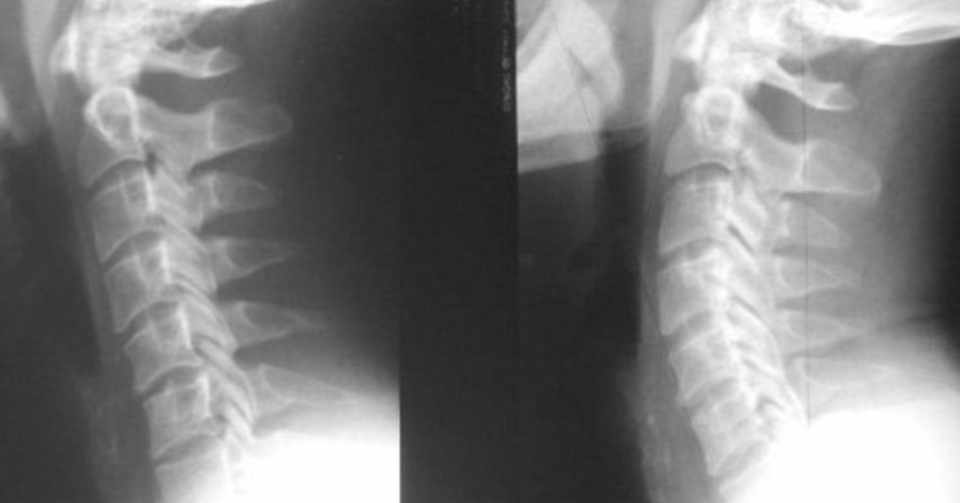

増えるストレートネック まっすぐ頸椎 本来頚椎(首の骨)は、30〜40度の湾曲があります。それが、長い間の姿勢の崩れや頚椎の疲労などによって、その湾曲がストレート=まっす になってしまう状態をストレートネックといいます。 『ストレートネック』になると、頭部の重心が前に移動し. 下に表示したレントゲン写真をご覧ください。 数年前の私の実際のレントゲン写真です。 私レントゲン写真(左)は、 ストレートネック で頸椎が真っすぐ。 通常(右)は 頸椎の自然なカーブ(彎曲)があります。 この状態では、筋肉は緊張しやすく、. 検証してみます。 なぜ人はストレートネックになってしまうのか? 人間の背骨は、以下の写真のように 頸椎(首の骨)は7個、胸椎(背中の骨)が12個、 腰椎(腰の骨)が5個で構成されています。.

ストレートネックとは,レントゲン上,クビの骨の配列が直線状になる事(頚椎の生理的前彎の消失)をいいます,長時間デスクワークを行う人に多く見られ,肩こりや頭痛の原因となります. 右の写真はストレートネックのレントゲン側面像 … "ストレートネック" の続きを読む. ストレートネックとは? 正常な首には、軽いソリがあります。 (レントゲン写真の右側) しかし、そのソリが少なくなったり、 あるいは無くなって(消失)し、 首が真っ直ぐになってしまった状態を.